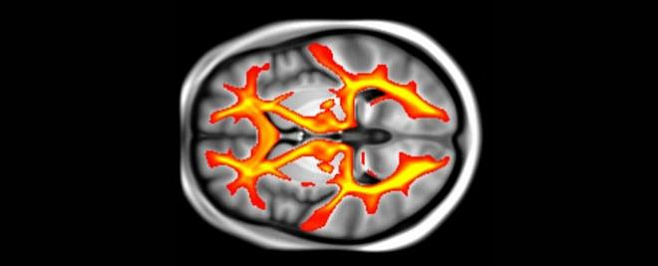

Ученые изучали результаты МРТ-сканирования мозга более 22000 человек, фиксируя изменения в сером и белом веществах мозга, а также записывая клинические, демографические и когнитивные данные участников.

«Мозг состоит из сетей, которые соединяют различные области и работают вместе, чтобы координировать мышление — эти области взаимодействуют посредством путей белого вещества, — пояснил автор исследования. — Мы обнаружили, что как на объем мозга в лобно-теменной сети, так и на целостность связей белого вещества между регионами воздействуют факторы риска, влияющие на кровоснабжение мозга».